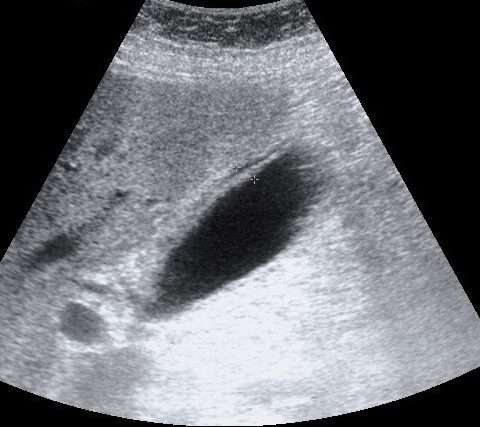

Las pruebas de imagen, las radiografías simples del abdomen pueden mostrar cálculos biliares radiopacos en aproximadamente el 15% de los casos, aunque esto no es suficientemente sensible para un diagnóstico definitivo. Por otro lado, la ecografía abdominal en el cuadrante superior derecho es una de las primeras pruebas de imagen realizadas. Aunque es sensible para detectar los cálculos biliares, su capacidad para diagnosticar colecistitis aguda es moderada, con una sensibilidad del 81% y una especificidad del 83%. Los hallazgos sugestivos de colecistitis aguda en ecografía incluyen engrosamiento de la pared de la vesícula biliar, líquido pericolecístico y un signo ecográfico de Murphy, que consiste en la aparición de dolor durante la compresión del área del hipocondrio derecho.